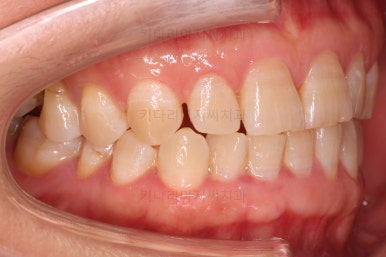

초진 때의 사진입니다.

전반적으로 치열이 삐뚤하고 불균일한 양상이긴 하지만 꼭 이런 부분들까지 교정해야 하는 건 아니에요.

치열에 대한 본인의 개선 의사가 있다면 전반적인 교정을 해줄 필요가 있지만, 그렇지 않다면 굳이 할 필요가 없는거죠.